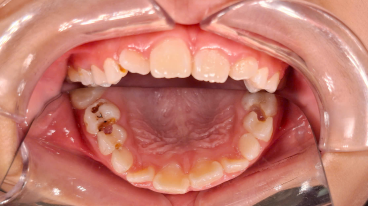

SSC (Stainless Steel Crown) là mão răng bằng thép không gỉ, được thiết kế sẵn với nhiều kích cỡ khác nhau, thường dùng để phục hồi răng sữa đã bị sâu lớn hoặc tổn thương nặng. Đây là một dạng phục hình toàn phần bao phủ toàn bộ thân răng, giúp bảo tồn và duy trì chức năng của răng sữa cho đến khi thay răng vĩnh viễn.

Duy trì được răng sữa đến đúng thời điểm thay răng, ngăn ngừa mất khoảng và sai lệch cung răng.

- Giúp răng giữ chức năng nhai, phát âm và thẩm mỹ trong giai đoạn phát triển.